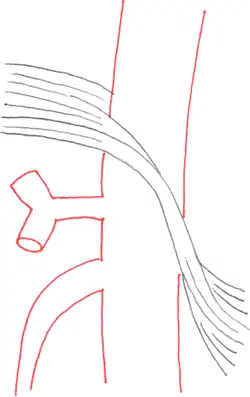

Anatomy

The median arcuate ligament is a ligament formed at the base of the diaphragm where the left and right diaphragmatic crura join near the 12th thoracic vertebra. This fibrous arch forms the anterior aspect of the aortic hiatus, through which the aorta, thoracic duct, and azygos vein pass. The median arcuate ligament usually comes into contact with the aorta above the branch point of the celiac artery. However, in up to one quarter of normal individuals, the median arcuate ligament passes in front of the celiac artery, compressing the celiac artery and nearby structures such as the celiac ganglia.[2] In some of these individuals, this compression is pathologic. It leads to the median arcuate ligament syndrome.[2]